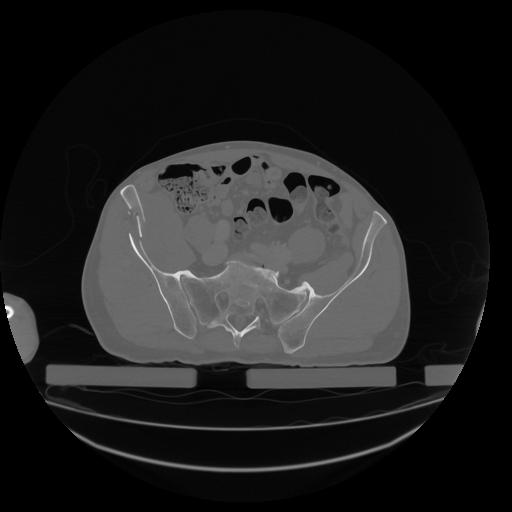

34 CUERPO,CE,Vol,1.0,CUERPO,,